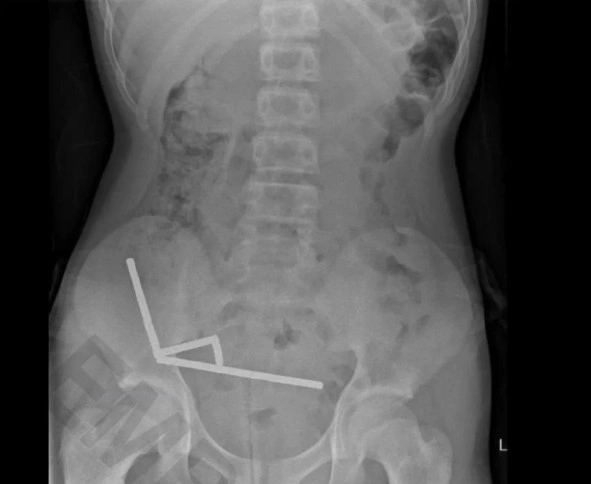

Hình ảnh X quang cho thấy nam châm trong bụng bé trai 13 tuổi. Ảnh: New Zealand Medical Journal

Khoảng 80-100 viên nam châm công suất cao được lấy ra trong ca phẫu thuật của bệnh nhân 13 tuổi. Ảnh: New Zealand Medical Journal